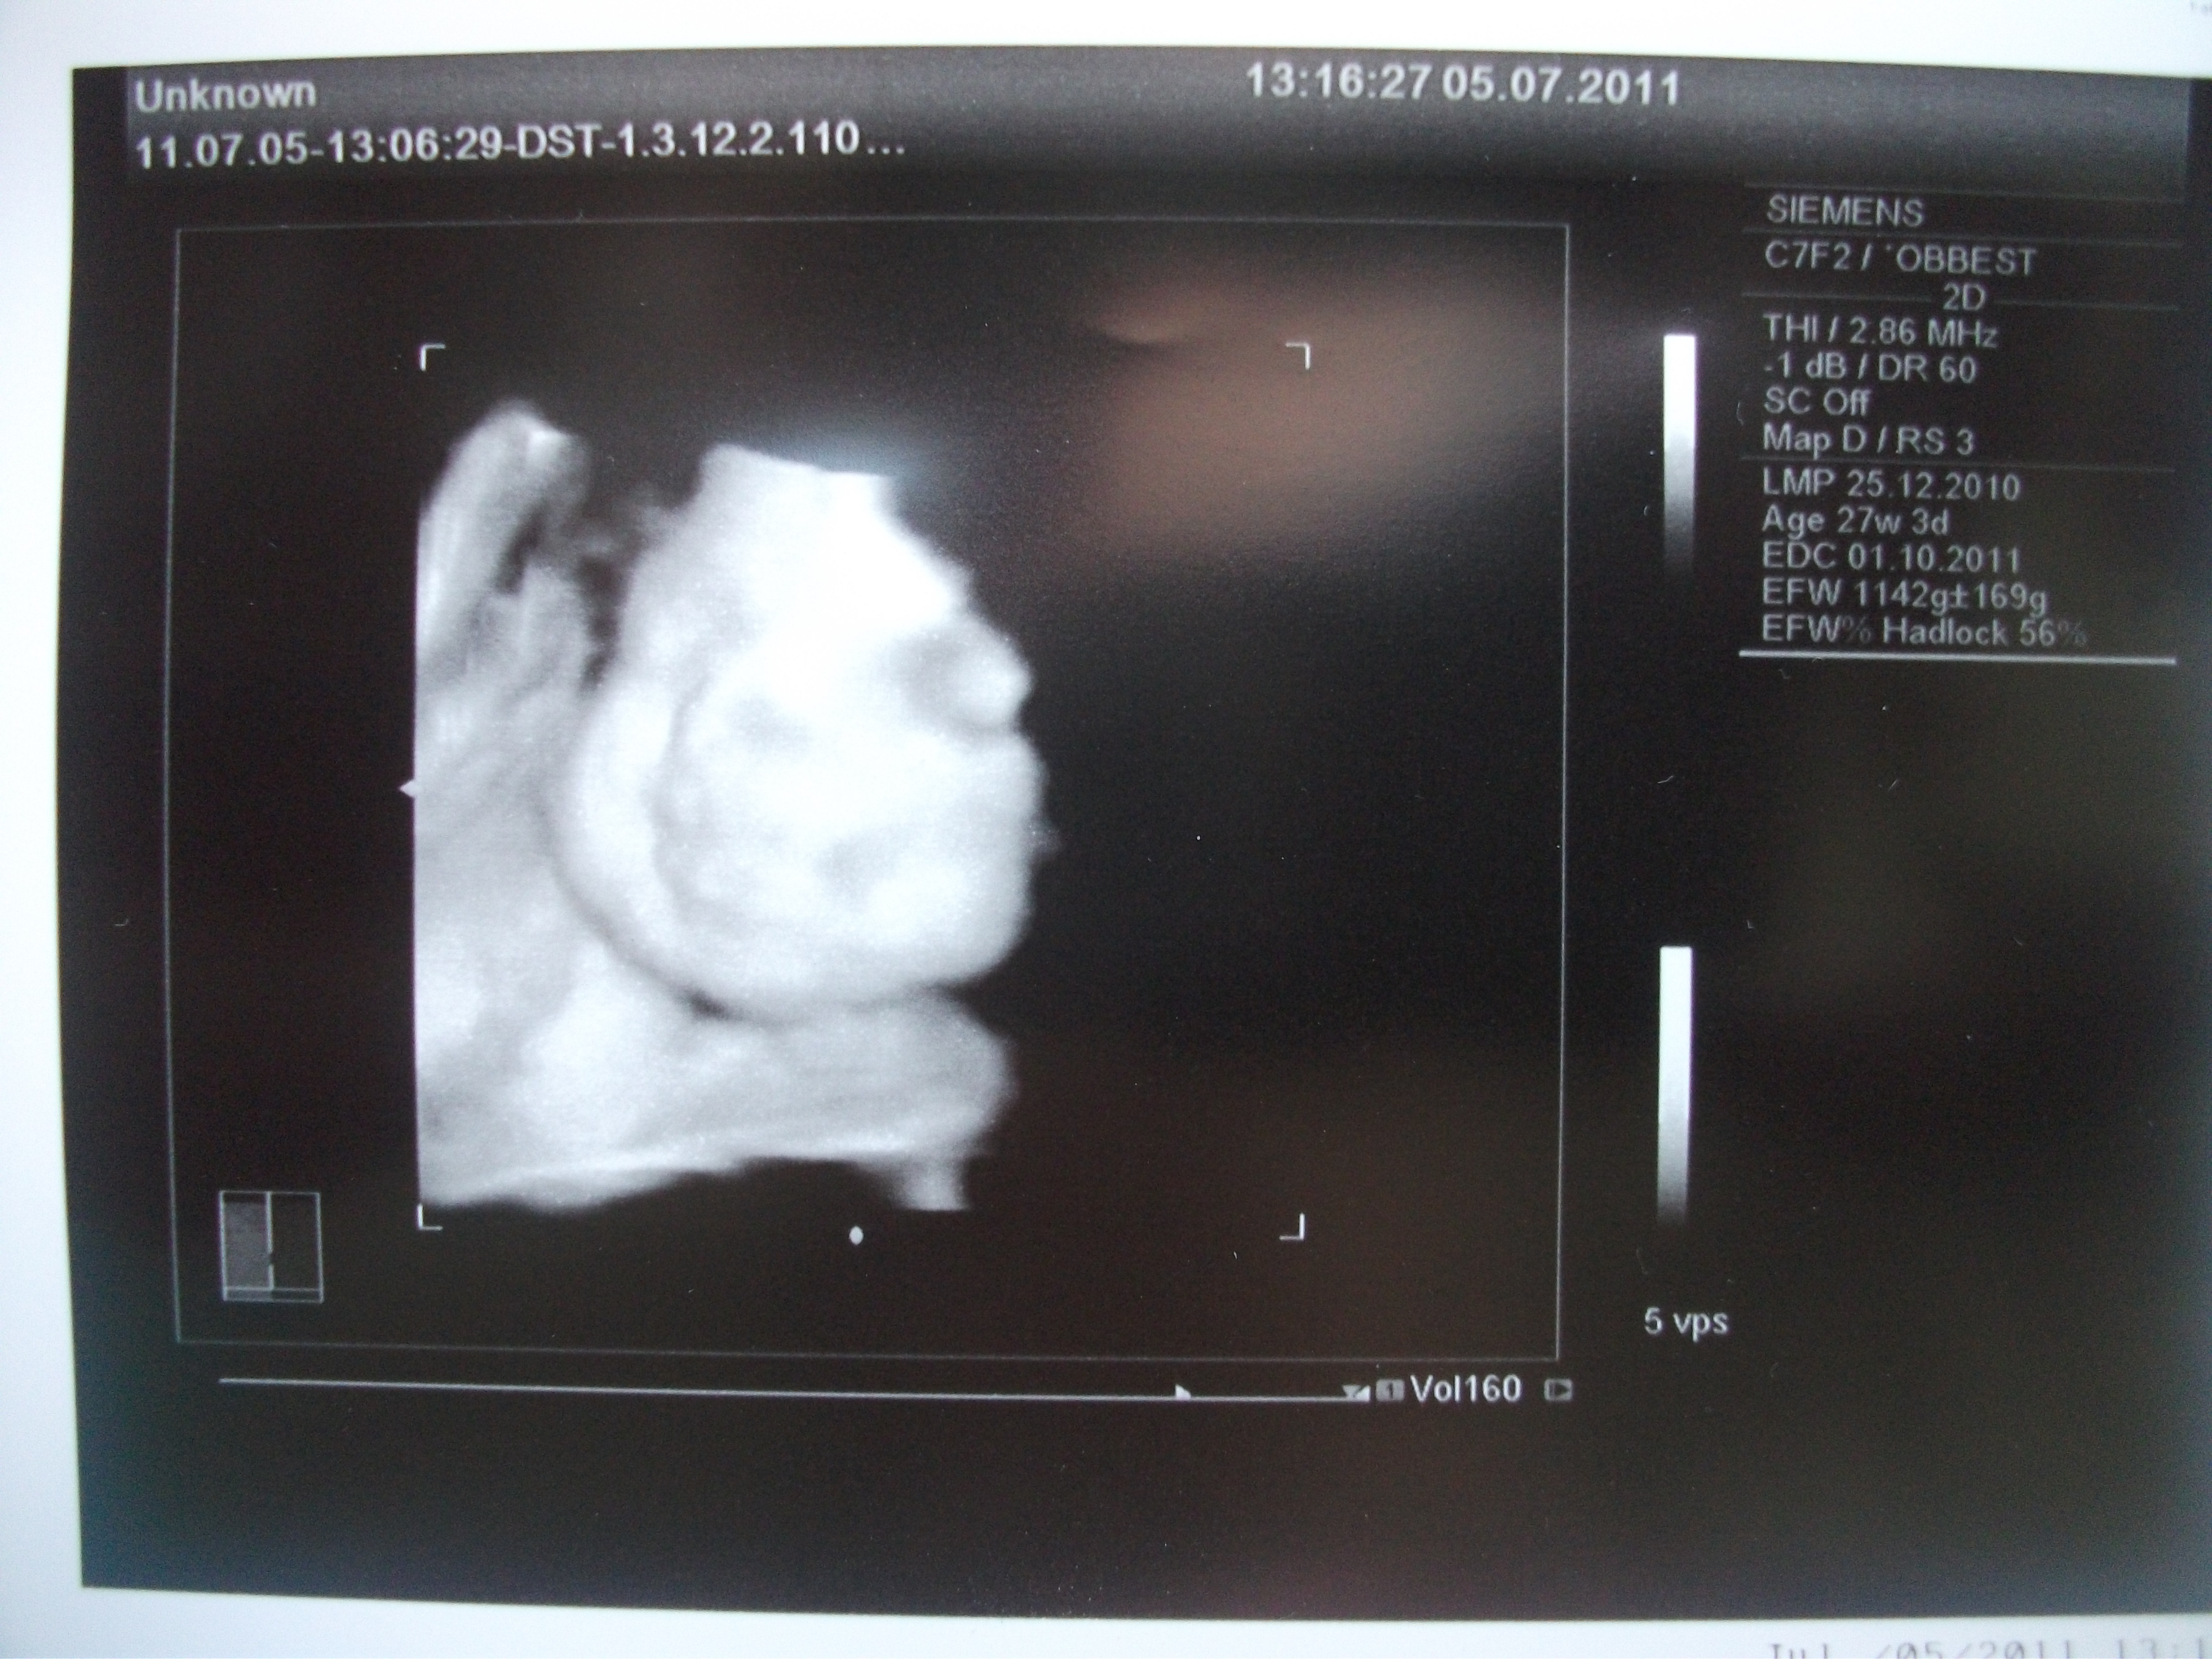

Here is a picture they took at the hospital last week. It is the first 3d ultrasound that I’ve gotten to see. It isn’t the greatest picture, but it’s so amazing to see this kind of technology. At the time they were doing the ultrasound, we saw her sucking on her fingers. How cool is that?